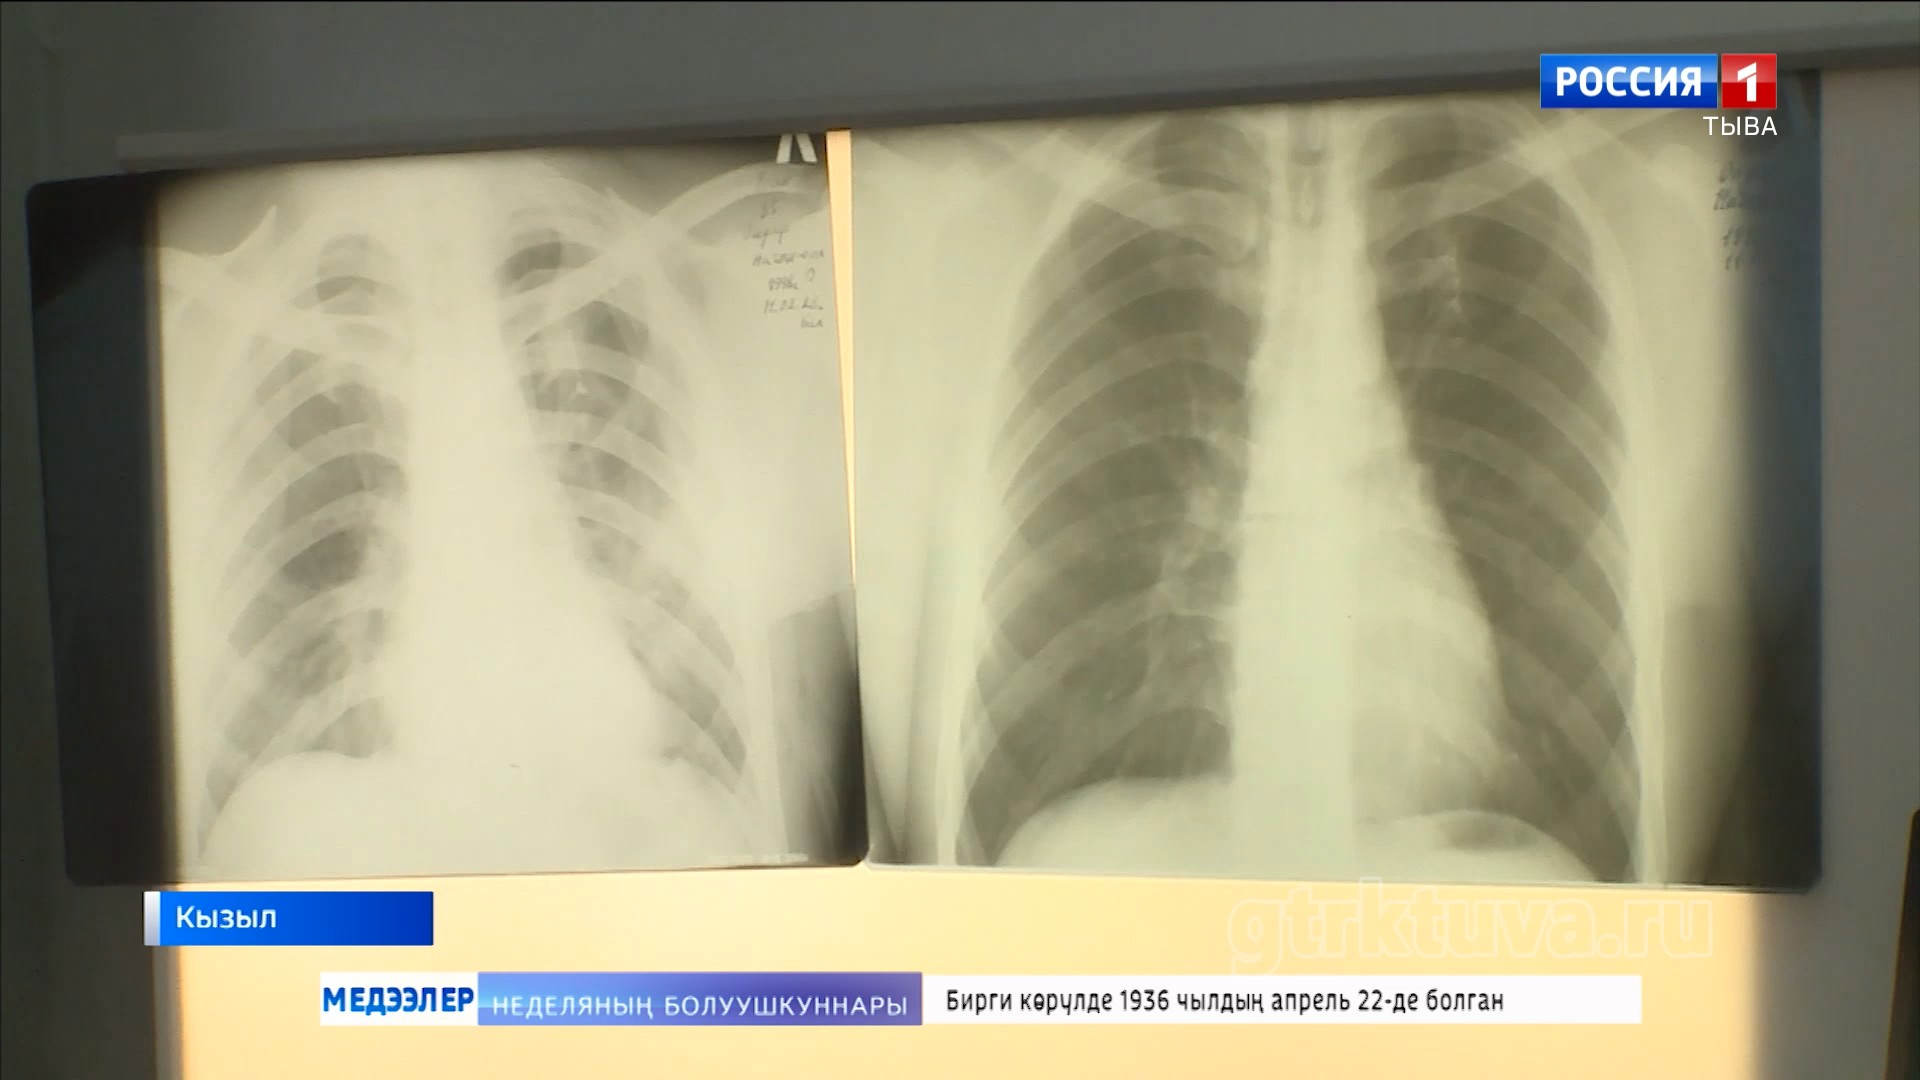

Өкпе аарыынга удур демисел

Тыва Россияда өкпе аарыының талазы-биле мурнуку одуругларда хөй чылдарның дургузунда чоруп орарын статистика көргүзүп турар. Социал аарыгларга хамаарыштырып турган туберкулез уе-шагның аайы-биле база өскерлип турар. Чогуур ужурлуг дериг-херексел, эм-таң-биле эмнелге хандыртынып турар. Удавас чаа оран-саваны база тудар. Эң кол чүве, аарыгны эмнээри берге-даа болза, үзе эмнеттинер, чүгле кижиниң бодунуң күзелинден хамааржыр. Аарыгны болдурбазы-биле профилактиканы чорудары чугула.

Март 24-те бүгү делегейде туберкулезка удур демисел хүнү. Аңаа тураскаадып, республикада өкпе аарыынга удур шалыпчы айны чарлаан. Фтизиатрлар көжүп чоруур мобильдиг хөрек тырттырар дерилгелиг автомашина-биле кожуун, сумуларны эргий кезип, найысылалдың аңгы-аңгы микрорайоннарынга чурттакчы чонну шинчилеп, көөр.